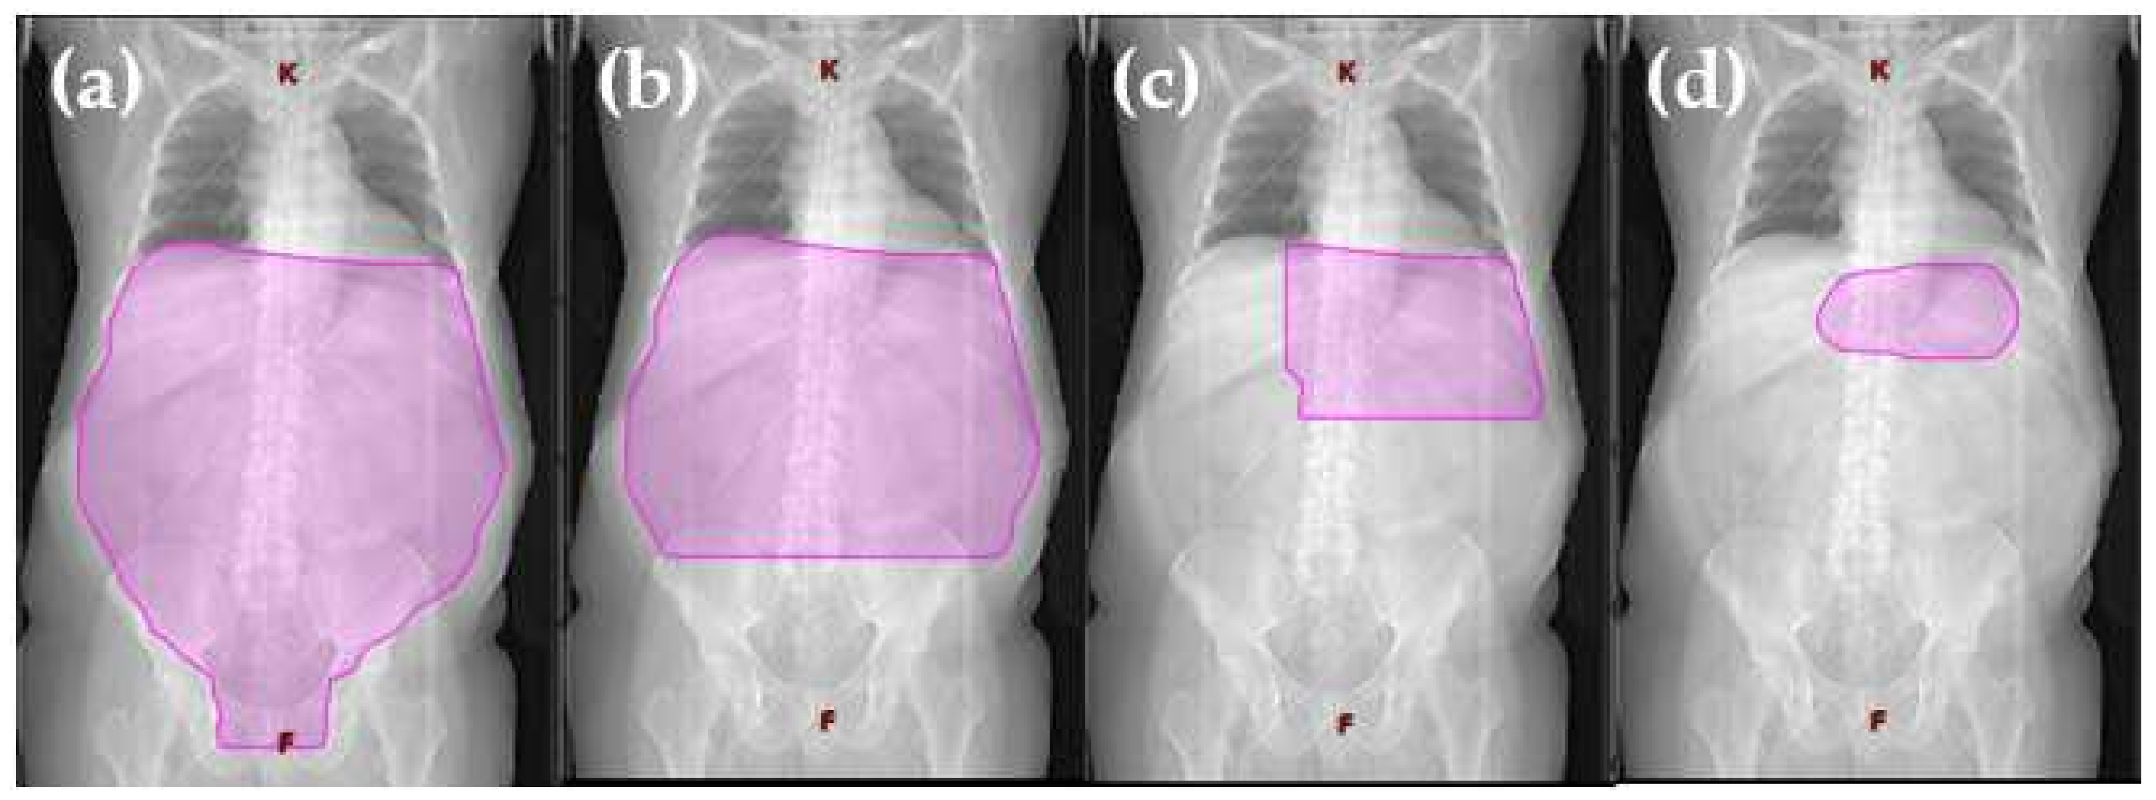

2. Extended Field Radiotherapy (EFRT)

3. Reduced Extended Field Radiotherapy

4. Involved Field Radiation Therapy (IFRT)

5. Involved Site Radiotherapy (ISRT)